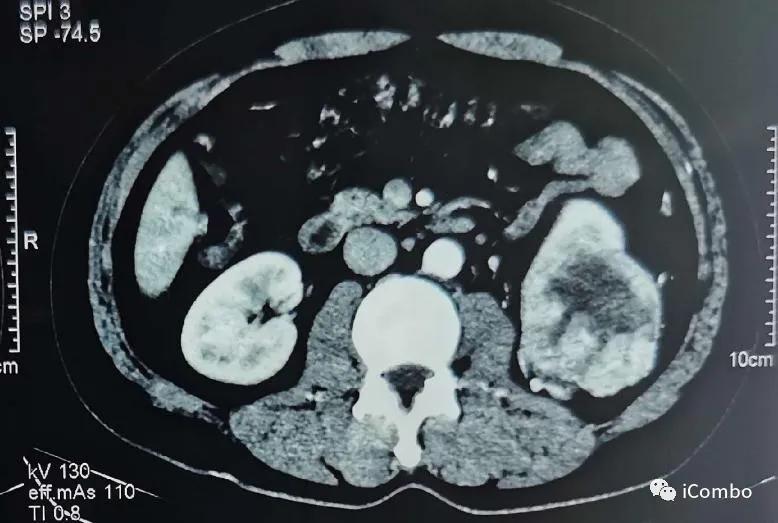

现病史:2012年行左肾癌根治术(肿瘤最大径7厘米),2018-9左髂部疼痛不适,考虑转移瘤,行索坦治疗。2019-06发现左胫骨肿块。2019-7-18 CT示肿瘤较前进展(107*84mm)。

CT:

2012年4月左肾癌根治术

2018.9左髂骨疼痛,穿刺确诊左髂骨转移